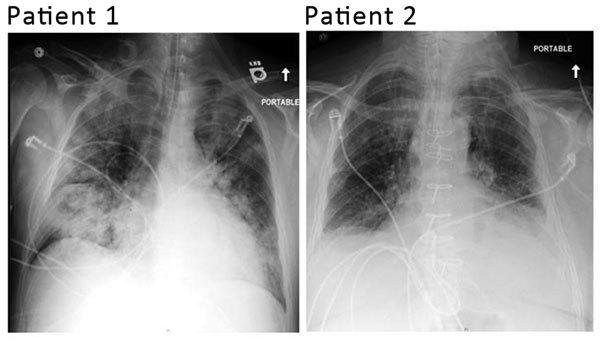

Human adenovirus 7d, a genomic variant with no reported circulation in the United States, was isolated from 2 adults with severe respiratory infections in Illinois. Molecular typing identified a close relationship with strains of the same genome type isolated from cases of respiratory disease in several provinces of China since 2009.

人腺病毒7d是一种在美国尚无传播报道的基因组变异体,从伊利诺伊州2名患有严重呼吸道感染的成年人中分离得到。分子分型显示,该病毒与自2009年以来在中国多个省份从呼吸道疾病病例中分离出的相同基因组类型的毒株关系密切。